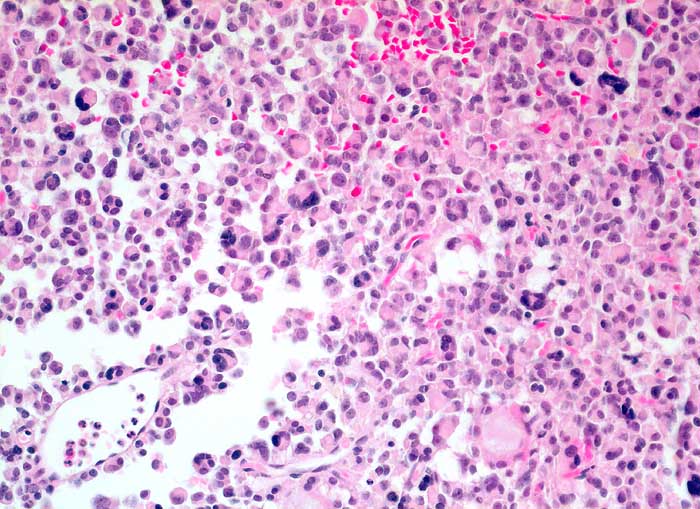

chromophobes Hypophysenadenom

benigner Tumor

Hypophyse, Vorderlappen

Diffus wachsendes Hypophysenadenom mit zahlreichen mehrkernigen Zellen

Über 50% der Adenomzellen zeigen eine Expression für das Wachstumshormon. Lediglich Einzelzellen positiv für den Marker gegen Prolactin. Die übrigen angewandten Marker vollständig negativ. Der MIB-1-Proliferationsindex liegt deutlich unter 1%

Hypophysenadenom, Vd. a. atypische Akromegalie.

200